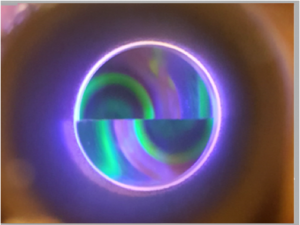

Gonioscopy